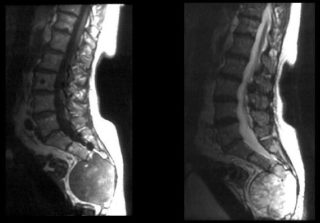

Остеобластома

Это опухоль в костях. Симптомы практически отсутствуют, но иногда появляются тупые боли. Если дискомфорта и косметического дефекта нет, врачи не настаивают на обязательном удалении. Повреждение костной ткани, воспаления, наследственность, пониженный иммунитет и переохлаждение могут стать причинами появления. Диагностика: рентген, КТ, МРТ.

- МРТ.

- КТ.

- КТ или МРТ назначаются при подозрении на метастазы;